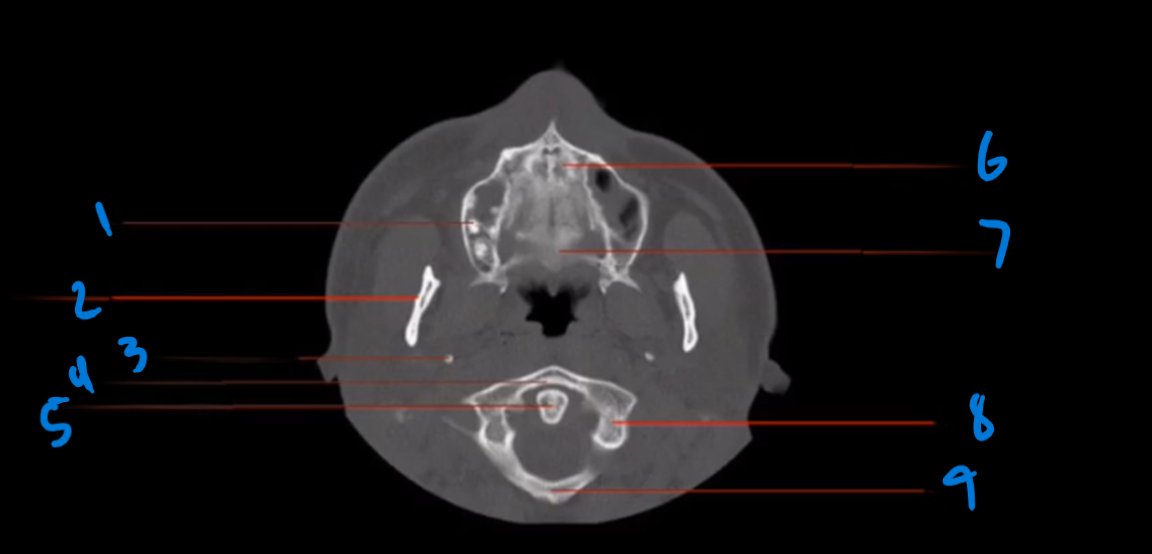

What is the landmark #1 called?

Nasal septum

What is landmark # 2 called?

Zygoma

What is landmark # 3 called?

Maxillary Sinus

WHat is landmark # 4 called?

Sphenoid Bone

What is landmark # 5 called?

Carotid Canal

Nasal bone

What is landmark # 6 called?

Maxillary Bone

WHat is landmark # 7 called?

Sphenoid Sinus

What is landmark # 8 called?

Mastoid air cells, Temporal bone

What is the zygomatic arch connecting to?

Facial and cranial bones

Landmark 1?

Landmark # 2

Landmark #3?

Coronoid process, mandible

Landmark # 4 called?

Mandibular condyle

Landmark # 5?

Landmark # 6?

Jugular Foramen

Landmark # 7?

Landmark # 8

Nasolacrimal duct

Landmark # 9

Landmark # 10

Zygomatic arch

Landmark # 11?

Clivus

Landmark # 12

External Auditory Meatus

Landmark # 13